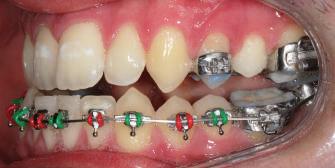

20 Dental Tribune Bulgarian Edition / октомври 2022 г. П ациентите със завършен растеж и скелетни проблеми обикновено представляват предизвикателство за ортодонт ската практика. Необходимостта от изваждане на зъби в комбинация с особеностите на възрастовата ортодонтия изисква особено внима ние. Фокусът върху критично важното значение на позицията на долните резци във връзка с дългосроч ната стабилност и постигането на оптимални оклузални взаимоотношения при затварянето на екстракционните пространства лесно може да излезе извън контрол. Когато към тези чисто кли нични проблеми се добави и стресът от натоваре ната практика, предизвикателството става още по-голямо. Всички тези фактори налагат използ ването на доказан подход с ясни и последовател ни стъпки, в което се разкрива силата на дисциплината „Алекзандър“ – предвидим протокол през целия процес на елиминиране на ротациите, ниве лиране на дъгите, затваряне на екстракционните пространства и финализиране на случая. Именно такъв е и случаят, който презентираме –екстракционен, скелетен клас 3 при възрастен па циент, лекуван по системата „Алекзандър“. ПРЕДВИДИМИ РЕЗУЛТАТИ ПРИ ПАЦИЕНТИ СЪС ЗАВЪРШЕН РАСТЕЖ И СКЕЛЕТЕН КЛАС 3, ИЗПОЛЗВАЙКИ ЕКСТРАКЦИОННО ЛЕЧЕНИЕ ПО ДИСЦИПЛИНАТА „АЛЕКЗАНДЪР“ Д-р Радой Димитров, България Преди започване на лечение клиничен случай | ортодонтия Фиг. 1а–1e Преди започване на лечение. Пациентът пристига в практиката с основното оплакване от невъзмож ност за нормално дъвчене. Снета е цялата необходима диагностична ин формация. Фиг. 1f–1h Снимки в профил и анфас. Фиг. 1i–1k Панорамна снимка, телерентгенография и анализ на телерент генография. Фиг. 1а Фиг. 1d Фиг. 1f Фиг. 1g Фиг. 1h Фиг. 1e Фиг. 1b Фиг. 1c Фиг. 1i Фиг. 1j Фиг. 1k

closed.

21Dental Tribune Bulgarian Edition / октомври 2022 г. ДИАГНОСТИЧНИ РЕЗУЛТАТИ: 1. Възраст на пациента: 21 години 2. Скелетен клас III (ANB 0) 3. Зъбен клас 3 4. Ръбцова захапка във фронта, кръстосана в дисталните участъци 5. Тясна горна челюст 6. Overjet – 0 мм, Overbite – 0 мм 7. Несъответствие на горната с долната средна линия 8. Единични контакти в ЦО 9. Хиподивергентен тип на растеж SN/MP – 33.5 10. Неравен гингивален контур 11. Неравна линия на усмивката 12. Тенденция за рецесии в долен фронт ПРЕПОРЪЧИТЕЛНО ЛЕЧЕНИЕ: Пълно ортодонтско лечение с метални брекети „Алекзандър“ Корекция на клас 3 захапката в областта на кучешките зъби с екстракция на първите пре молари в долна челюст Корекция на кръстосаната захапка в дистални участъци Коригиране на ръбцовата захапка във фронта Подобряване на ОJ и OB на пациента Стрипинг в долен фронт Подреждане на зъбите в горната и долната челюст Професионално хигиенизиране и профилактични дентални прегледи са препоръчителни на всеки 6 месеца. 1-ви месец След 1 месец са залепени брекети в горната челюст – поставена е еластична дъга. 016 NiTi. В долната челюст са елиминирани ротациите, поставена е стоманена дъга. 016SS, закалена с ток, и еластична верижка за затваряне на пространствата. 3-ти месец В долната челюст е поставена трета дъга – 17 x 25 NiTi с къси лигатури и верижка

В горната челюст се затварят пространствата с дъга .016SS и верижка. 5-и месец На 5-ия месец след залепяне на брекетите в долната челюст е поставена стоманена дъга 16 x 22 SS с четвъртито сечение, омега луп и тай бек. В горната челюст е поставена дъга 17 x 25 NiTi. Поради липсата на стабилни оклузални контакти са поставени лингвални верижки в областта на моларите, за да се предотврати нежелана ротация на 7-ите зъби. 6-и месец На 6-ия месец от началото на лечението са екстрахирани долните първи премолари, поставена е дъга 16 x 22 SS със затваряща чупка teardrop. Чупката се активира всеки месец по 1 мм с чинч-бек. клиничен случай | ортодонтия СТЪПКИ НА ЛЕЧЕНИЕТО Начало на лечението Лечението започва с поставяне на апарат за бърза експанзия в горната челюст. През първия месец от лечението са направени 24 оборота на апарата за експанзия. Залепени са брекети в долната челюст, поставена е дъга 17x25 CuNiTi, като са предпи сани клас 3 ластици (1/4”,4 1/2 oz) по време на сън, за да се осигури контрол върху торка на долните резци. Фиг. 2а Фиг. 3a Фиг. 4a Фиг. 3b Фиг. 4b Фиг. 3c Фиг. 4c Фиг. 3d Фиг. 4d Фиг. 3e Фиг. 4e Фиг. 5a Фиг. 5b Фиг. 5c Фиг. 5d Фиг. 5e Фиг. 6a Фиг. 6b Фиг. 6c Фиг. 6d Фиг. 6e Фиг. 7a Фиг. 7b Фиг. 7c Фиг. 7d Фиг. 7e Фиг. 2b Фиг. 2c Фиг. 2d

Dental Tribune Bulgarian Edition / октомври 2022 г.22 клиничен случай | ортодонтия 14-и месец В горната и долната челюст са поставени последни стоманени дъга с омега луп и тай бек – 17 x 25 SS с четвъртито сечение. Назначени е ластик за средната линия в комбинация с клас 3 ластик (1/4”, 6 1/2 oz). Контролни рентгенографии 13-и месец Екстракционните пространства са затворени. Направена е контролна панорамна снимка за оценка позицията на корените. Взето е решение за презалепване на брекетите на 12, 22 и пръстените на 36 и 46. 21-ви месец Средната линия в горната и долната челюст съвпадат. Ластиците са спрени. Свалени са пръстените и брекетите в горната и долната челюст, зигзаг ластици не са използвани поради благоприятните оклузални взаимоотношения. Фиг. 11j Ортопантомография в края на лечението. Фиг. 11k Телерентгенография след края на лечението. Фиг. 11l Анализ на телерентгенографията след лечението. Фиг. 11m Последователност на дъгите в горната и долната челюст Фиг. 11n Суперимпозиция на PreOp и PostOp ортопантомографии. 10-и месец Затварянето на пространствата е предвидимо и контролирано, без да се отварят пространства в зъбната дъга. Фиг. 8a Фиг. 8b Фиг. 8c Фиг. 8d Фиг. 8e Фиг. 10a Фиг. 10b Фиг. 10c Фиг. 10d Фиг. 10e Фиг. 9a Фиг. 9b Фиг. 9c Фиг. 9d Фиг. 9e Фиг. 9f Фиг. 11a Фиг. 11f Фиг. 11j Фиг. 11l Фиг. 11m Фиг. 11n Фиг. 11k Фиг. 11g Фиг. 11h Фиг. 11i Фиг. 11b Фиг. 11c Фиг. 11d Фиг. 11e

Dental Tribune Bulgarian Edition / октомври 2022 г. 23клиничен случай | ортодонтия реклама Лечението е продължило 21 месеца. Проведено е домашно избелване с индивидуални шини. За автора: Д-р Радой Димитров завършва с отличие Факултета по дентална медицина към МУ–София през 2015 г. В продължение на 5 години работи в няколко водещи практики в София, като през 2019 г. заедно със своята съпру га д-р Траяна Димитрова основават собствена практика в гр. Гоце Делчев –Dimitrovi Dental Care. Посещава редица курсове за повишаване на квалификаци ята, но най-сериозен тласък в развитието на ортодонтската си практика получава след завършването на комплексната ортодонтска програма, воде на от д-р Иван Горялов, базирана на дисциплината „Алекзандър“ – система с повече от 50 години опит в целия свят. Д-р Димитров е член на Българския изследователски клуб „Алекзандър“. Взе ма участие като гост-лектор в симпозиума с международно участие The Power of the Alexander Discipline, който се проведе на 14–15.05.2022 г. С д-р Ди митров можете да свържете на тел. +359885 252 025. Заключение Представеният случай е ярък пример за възможностите и красо тата на дисциплината „Алекзандър“ – приложен е утвърден под ход с ясни правила и са постигнати очакваните цели. Резулта тът ще бъде дългосрочно стабилен, тъй като са спазени всички правила, които се отнасят към максимално комфортната пози ция на зъбите в края на лечението. Постигнати са красива усмив ка и стабилна оклузия. ПОСТИГНАТИ РЕЗУЛТАТИ ОТ ЛЕЧЕНИЕТО 1. Коригирана ръбцова захапка 2. Коригирана клас 3 захапка в областта на ку чешките зъби 3. Коригирана кръстосана захапка в дисталните участъци 4. Коригиран овърджет и овърбайт 5. Разширена е горната зъбна дъга 6. Подредени зъби в горната и долната челюст 7. Постигната е стабилна захапка с множество контакти в ЦО 8. Драматично е подобрена дъвкателната функ ция 9. Подобрена е линията на усмивката ДРУГИ ПРОВЕДЕНИ ДЕНТАЛНИ ПРОЦЕДУРИ 1. Домашно избелване на зъбите 2. Екстракция на мъдреците Фиг. 12a Фиг. 12b Фиг. 12c Фиг. 12eФиг. 12d Фиг. 12f Фиг. 12g Информация за дати, цени и отстъпки www.bracescourses.com 0889 22 55 01 Практически курсове лектор д-р Иван Горялов Дисциплината „Алекзандър“ ПЪТЯТ КЪМ СУПЕРУСМИВКИТЕ 100% връщане на цялата сума, ако не сте удовлетворени след преминаване на Ниво 1 Директно и индиректно залепяне на брекети Анализ, диагноза и план на лечение Лечение на клас 2 дълбока захапка Екстракционно лечение Лечение на клас 3 отворена захапка НИВО 5НИВО 1 НИВО 2 НИВО 3 НИВО 4